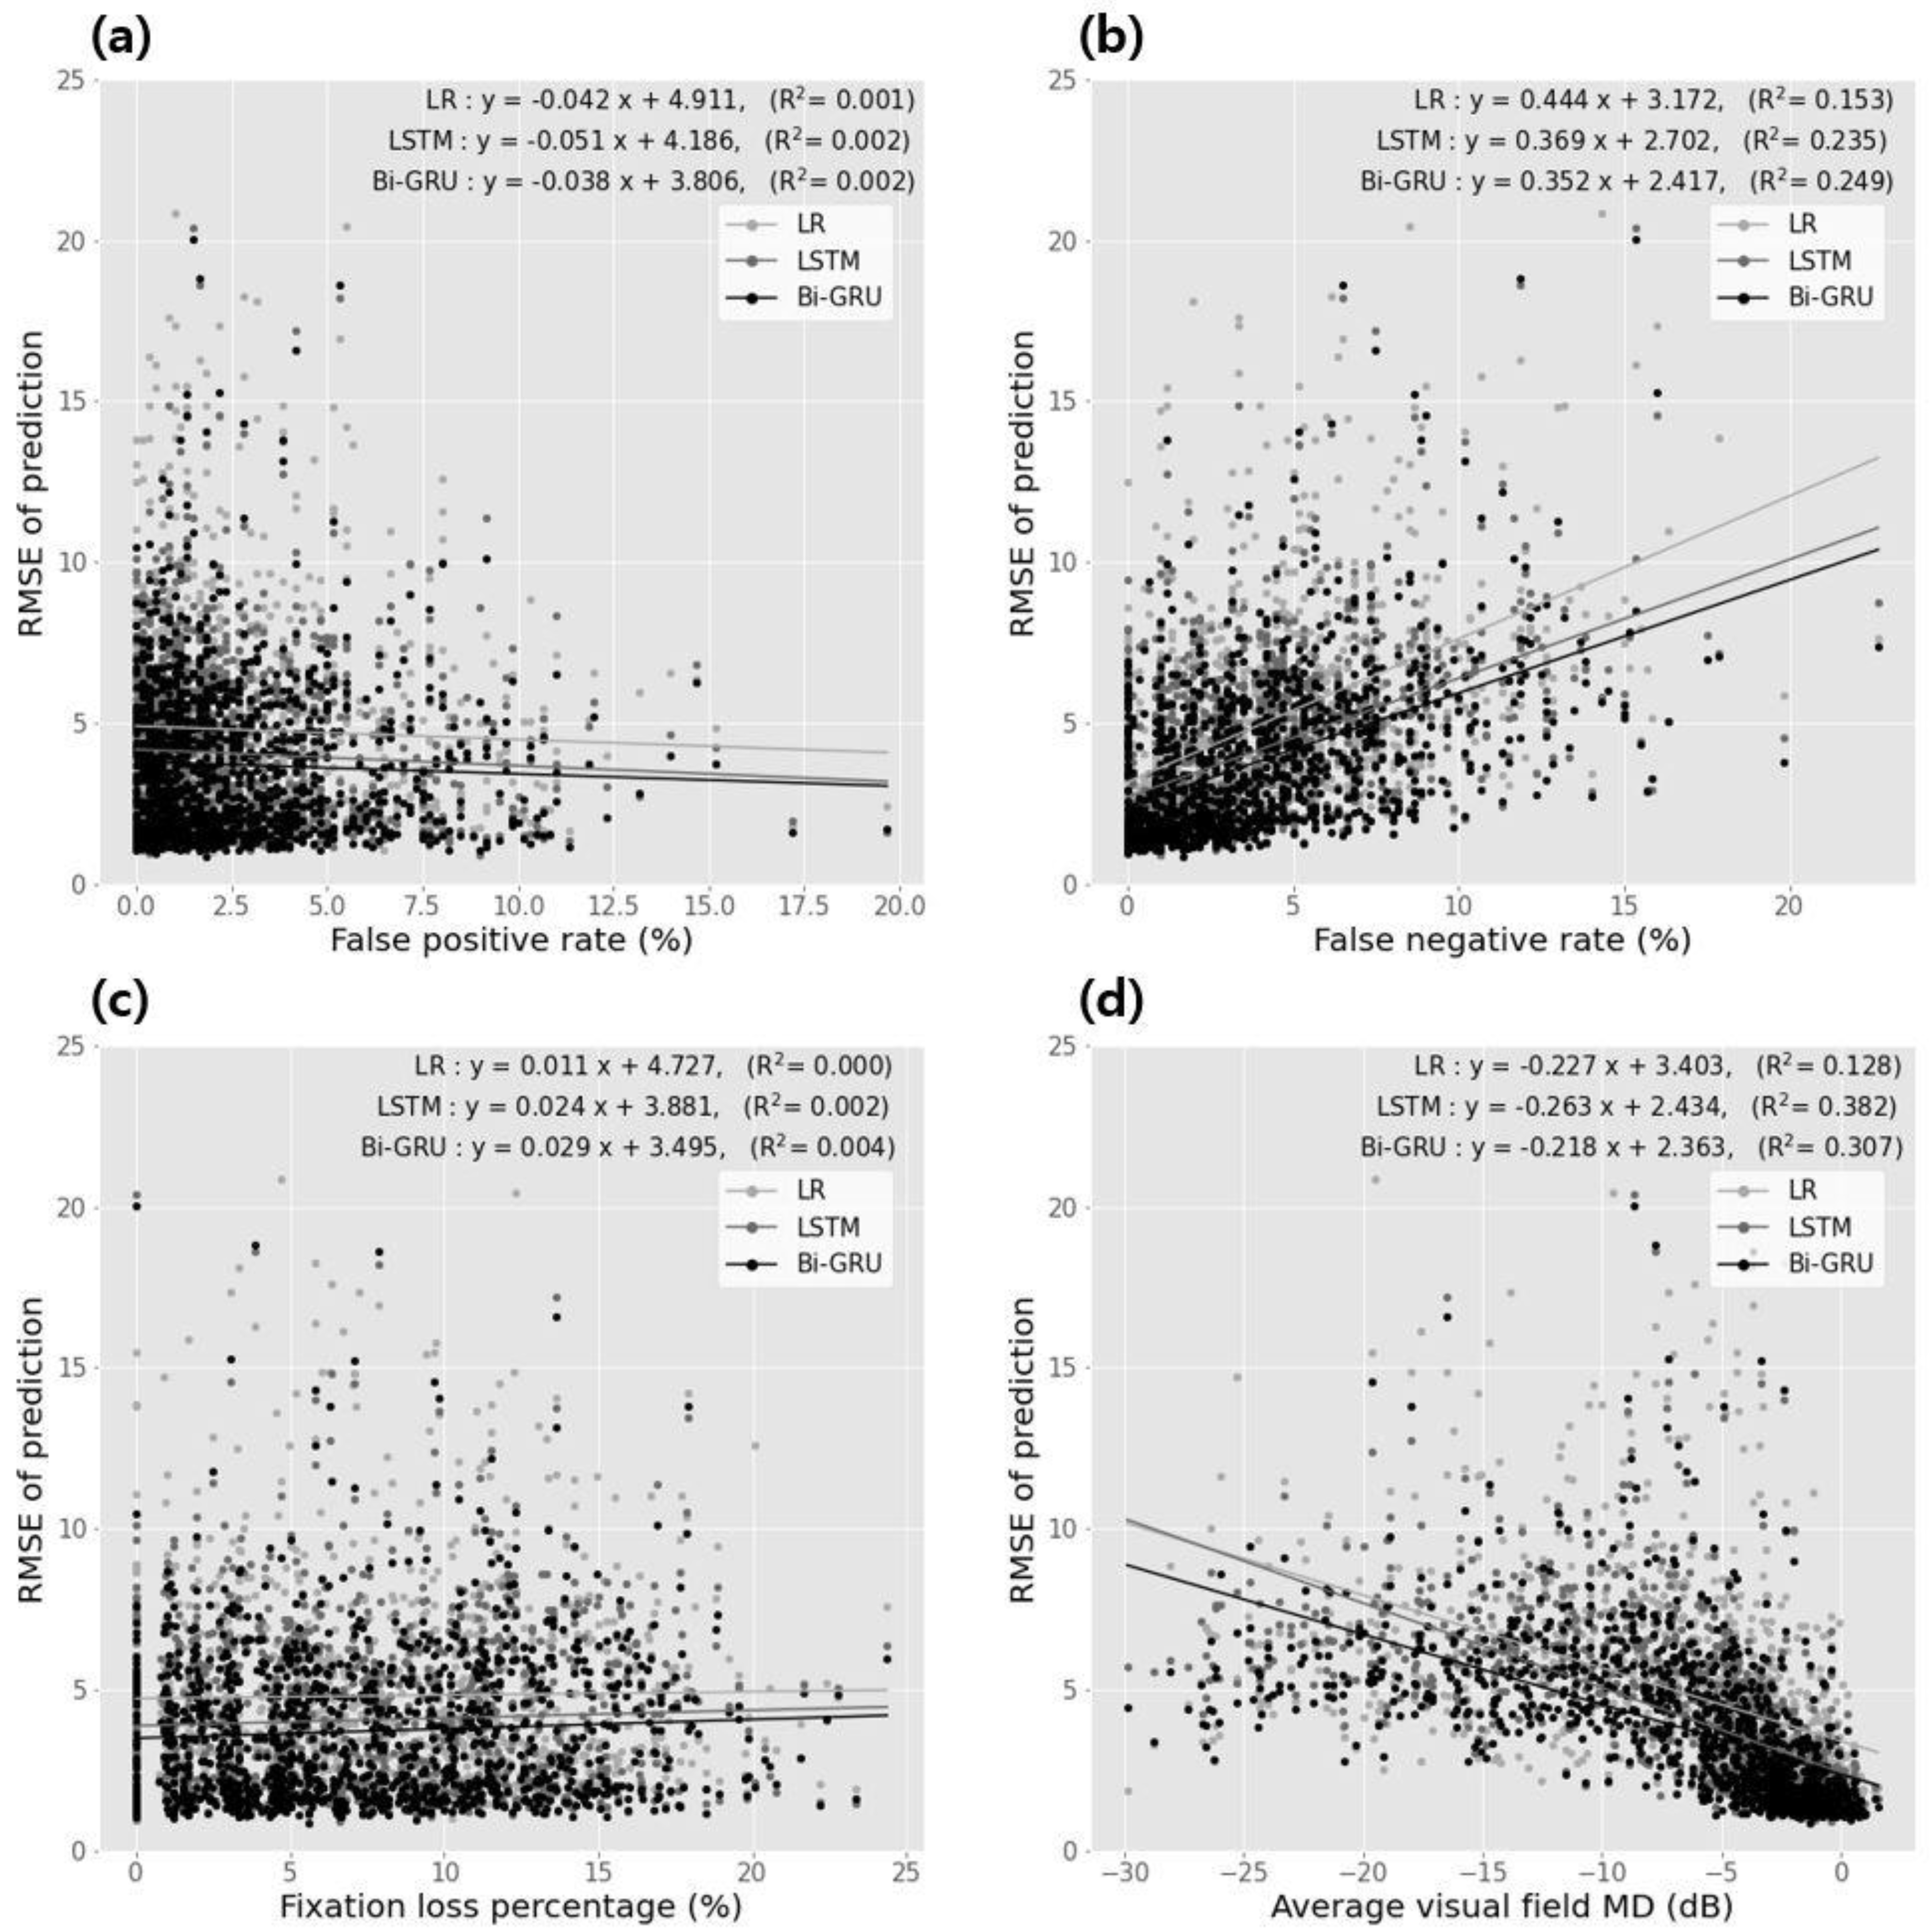

| Correlation Coefficients | Linear Regression Analysis | |||||

| classification error vs. false positive rate | ||||||

| Regression method | −0.024 | 0.344 | −0.042 | 4.911 | 0.001 | 0.329 |

| HMM | −0.043 | 0.040 | −0.041 | 4.184 | 0.002 | 0.048 |

| R-CNN | −0.042 | 0.134 | −0.038 | 3.804 | 0.002 | 0.141 |

| classification error vs. false negative rate | ||||||

| regression method | 0.444 | <0.001 | 0.444 | 3.142 | 0.143 | <0.001 |

| HMM | 0.443 | <0.001 | 0.349 | 2.402 | 0.234 | <0.001 |

| R-CNN | 0.448 | <0.001 | 0.342 | 2.414 | 0.249 | <0.001 |

| classification error vs. fixation loss percentage | ||||||

| regression method | 0.083 | 0.003 | 0.011 | 4.424 | <0.001 | 0.424 |

| HMM | 0.041 | 0.029 | 0.024 | 3.881 | 0.002 | 0.101 |

| R-CNN | 0.044 | 0.004 | 0.029 | 3.494 | 0.004 | 0.032 |

| classification error vs. average visual field average deviation | ||||||

| regression method | −0.441 | <0.001 | −0.224 | 3.403 | 0.128 | <0.001 |

| HMM | −0.443 | <0.001 | −0.243 | 2.434 | 0.382 | <0.001 |

| R-CNN | −0.444 | <0.001 | −0.218 | 2.343 | 0.304 | <0.001 |